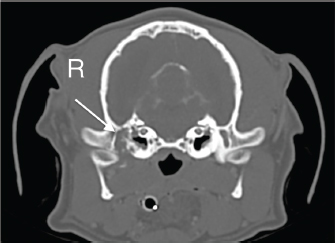

The CT images of the head revealed an extensive but circumscribed lytic lesion in the pars petrosa of the right temporal bone, leading to a pathologic fracture of the right temporomandibular joint condyle. The right masseter muscle enhanced focally (iomeprol at a dose of 400 mg/kg IV), and the right tympanic bullae had a ventral isoattenuating meniscus (Fig. 2). No abnormalities were detected in thoracic radiographs or abdominal CT.

Fig. 2. Computer tomography transverse image of the head showing an extensive but circumscribed lytic lesion in the pars petrosa of the right temporal bone and a pathologic fracture of the right temporomandibular joint condyle with caudodorsal displacement of the distal fragment.